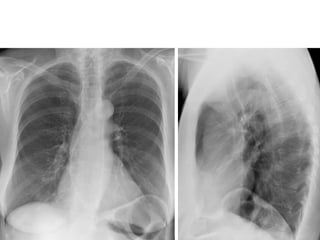

Pulmonary manifestations of

scleroderma

Bibasilar interstitial lung disease:

• Ground glass opacification.

• Reticular opacities & interlobular septal

thickening.

• Honey combing & traction bronchiectasis.

NO pleural effusion (DD with Rh & SLE).